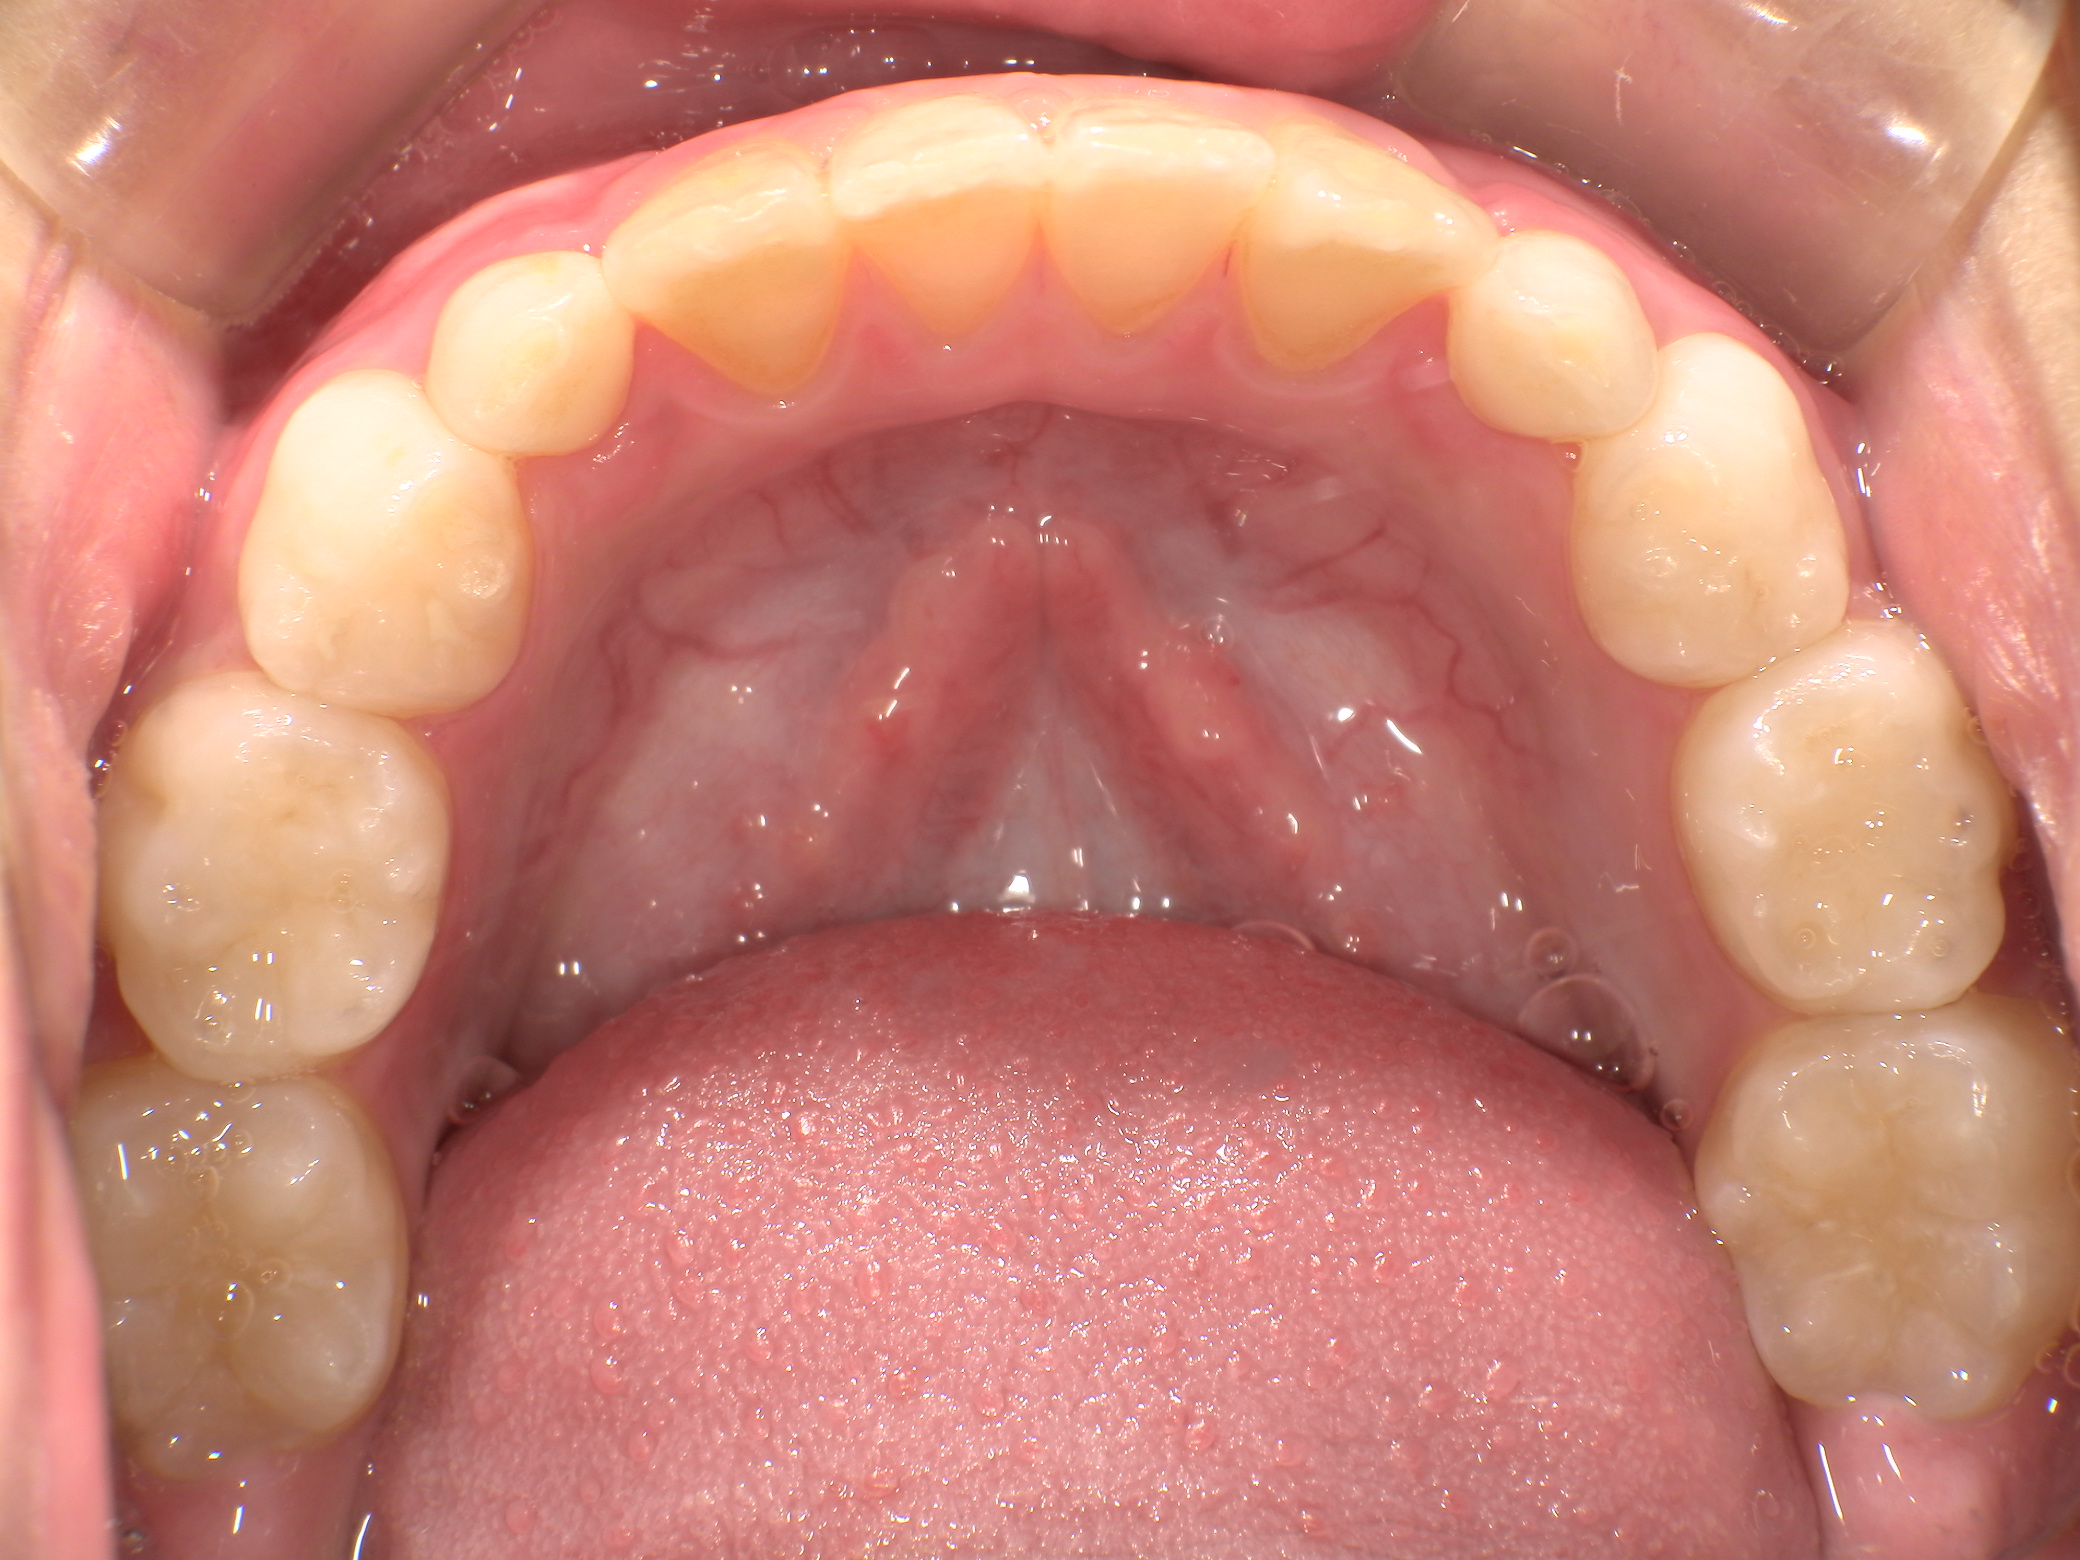

| 年齢・性別 | 8歳9ヶ月の女児 |

|---|---|

| 主訴 | 歯並びの乱れを気にされて来院された患者様です。将来的なスペース不足と歯のねじれ(翼状捻転)が懸念されました。 |

| 治療期間・回数 | 2年10ヶ月・19回 |

| 費用 | 430,000円(税別) |